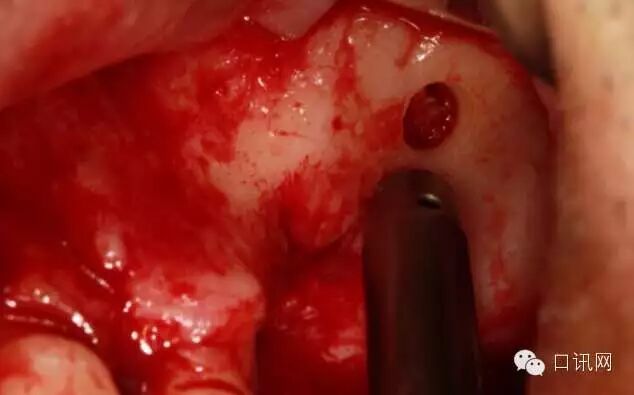

用永磁钻内提升钻刺透上颌窦颊侧骨壁口腔种植,口腔正畸医生

轻轻剥离洞口边缘窦膜熟悉掌握方丝工矫正技术,

使用1——2ml盐水(CAS内提升工具),水压将颊侧窦膜与骨壁剥离熟练掌握口腔内科治疗,

此时颊侧窦膜与骨壁已经分离,所以在使用器械将洞口扩大就会变得很安全,不会伤及窦膜中华人民共和国执业医师法